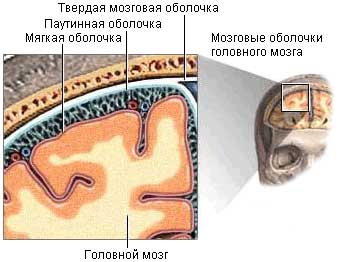

Арахноидит, затрагивающий головной или спинной мозг, представляет собой серозное воспаление уникальной структуры, находящейся между твердой верхней оболочкой и глубокой мягкой. Эта структура, напоминающая тонкую паутину, и получила название паутинная оболочка. Она образована соединительной тканью и образует настолько тесную связь с мягкой оболочкой мозга, что их часто рассматривают как единое целое.

Паутинная оболочка отделена от мягкой оболочки субарахноидальным пространством, в котором находится спинномозговая жидкость. В этом пространстве располагаются кровеносные сосуды, обеспечивающие питание данной структуры.

Из-за особенностей своего строения воспаление паутинной оболочки не бывает локализованным и охватывает всю систему. Инфекция может проникать сюда через твердую или мягкую оболочку.

Воспалительный процесс при арахноидите проявляется в виде утолщения и помутнения оболочки. Между сосудами и паутинной структурой образуются спайки, что затрудняет циркуляцию спинномозговой жидкости. Со временем могут формироваться арахноидальные кисты.